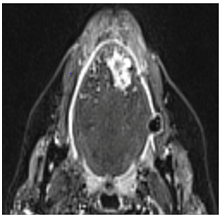

A follow-up PET scan was undertaken following scalp lesion excision, showing widespread metastatic disease in bone (primarily lumbar spine) and lung, and MRI highlighted a right fundal lesion (orbit), as well as right occipital and cerebellar metastases. These were treated with palliative radiotherapy (20 Gy in 5 fractions). Repeat CT neck, thorax, and abdomen was subsequently performed, demonstrating a mild reduction of metastatic disease within the occipital lobe, cerebellum and right orbit. However, a new finding of a polypoidal soft tissue thickening in the trachea at the level of the cricoid was also noted (Figure 3). The otolaryngologically asymptomatic patient therefore received clinical review in the head and neck clinic, where flexible nasal laryngoscopy revealed an obvious polypoidal swelling in the right subglottis. A laryngotracheal lesion had not been encountered in previous imaging studies, nor during previous procedures or clinical examinations, thus were the clinical features consistent with metastatic ACC.

Figure 3 Axial CT scan showing a Polypoidal Soft Tissue Thickening in the Trachea at the Level of the Cricoid.